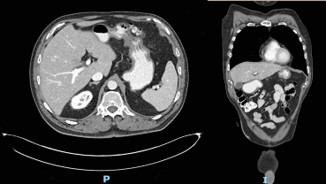

The patient followed an excellent clinical course, with full resolution of the symptoms after three months of treatment. The follow-up CT scan obtained three months (Figure 3) and six months (Figure 4) after admission revealed the complete dissolution of the bezoar. Annual clinical follow-up was performed until June 2025, with no recurrence of symptoms of bezoar reformation.

Figure 4: Computed tomography scan at six-month follow-up.